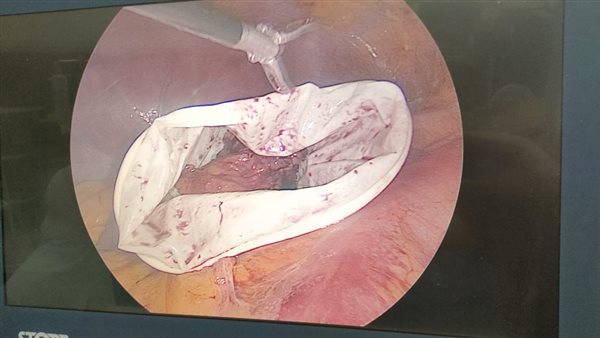

وأضاف سليمان: تم إجراء الجراحة للمريض باستخدام تقنية المنظار الجراحى، وهى أحدث التقنيات العلاجية المستخدمة في هذا المجال، حيث تم استئصال الورم من الغدة الكظرية اليسرى بجانب استئصال المرارة، لافتا إلى استقرار الحالة الصحية للمريض وخروجه من المستشفى بعد متابعة حالته الصحية.